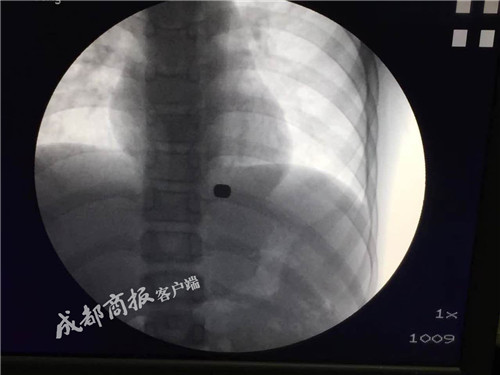

11月7日上午11点,麻醉后的强强被推进手术室,胡兵先用内镜从他的食道伸进去,轻轻拨开包裹着两块磁铁的组织,然后再把严格消毒后的“磁王”套上一根细线,用内镜缓缓送到强强体内的磁铁旁。不出所料,一个小时后两块磁铁被成功取出。